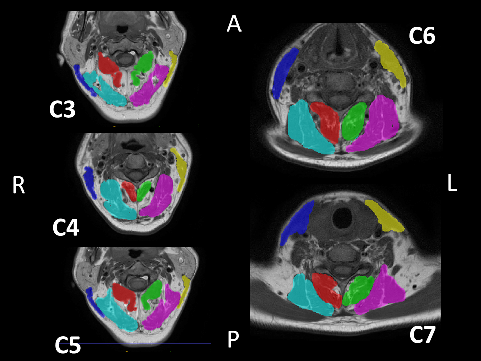

A semi-automatic segmentation software, ITK-SNAP (http://www.itksnap.org/pmwiki/pmwiki.php), was used to generate a 3D model of the sternocleidomastoid (SCM), splenius capitis (SPLC), SC–semispinalis capitis (SCP), and M muscles within the C3–C7 range, as well as to calculate their volumes (Figure 2,Figure 3). The MRI files were converted from the Digital Imaging and Communications in Medicine (DICOM) format to the Neuroimaging Informatics Technology Initiative (NIfTI) format using dcm2niix software (https://people.cas.sc.edu/rorden/mricron/dcm2nii.html).31 Subsequently, the files were uploaded to ITK-SNAP, where the boundaries of the deep neck muscles and the SCM muscle were delineated in 3D coordinates. For each scan, the boundaries of the muscles were determined using the active contour segmentation method. The muscle body contrast was created using the clustering 3/1 option, and the adipose tissue contrast was created using the clustering 3/2 option.32, 33 Each muscle and adipose tissue region was enclosed in a bubble created within the ITK-SNAP interface, and the 3D model was filled by determining the processor speed. The volumes were recorded in mm3 from the volumes and statistics tab of the software.34 All measurements were performed by the same investigator who was blinded to the study groups.